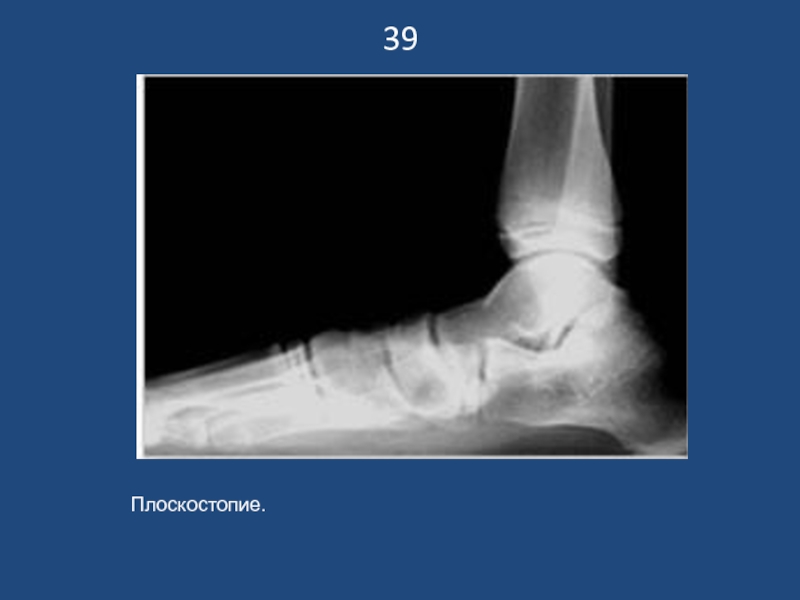

Плоскостопие.

39Плоскостопие.